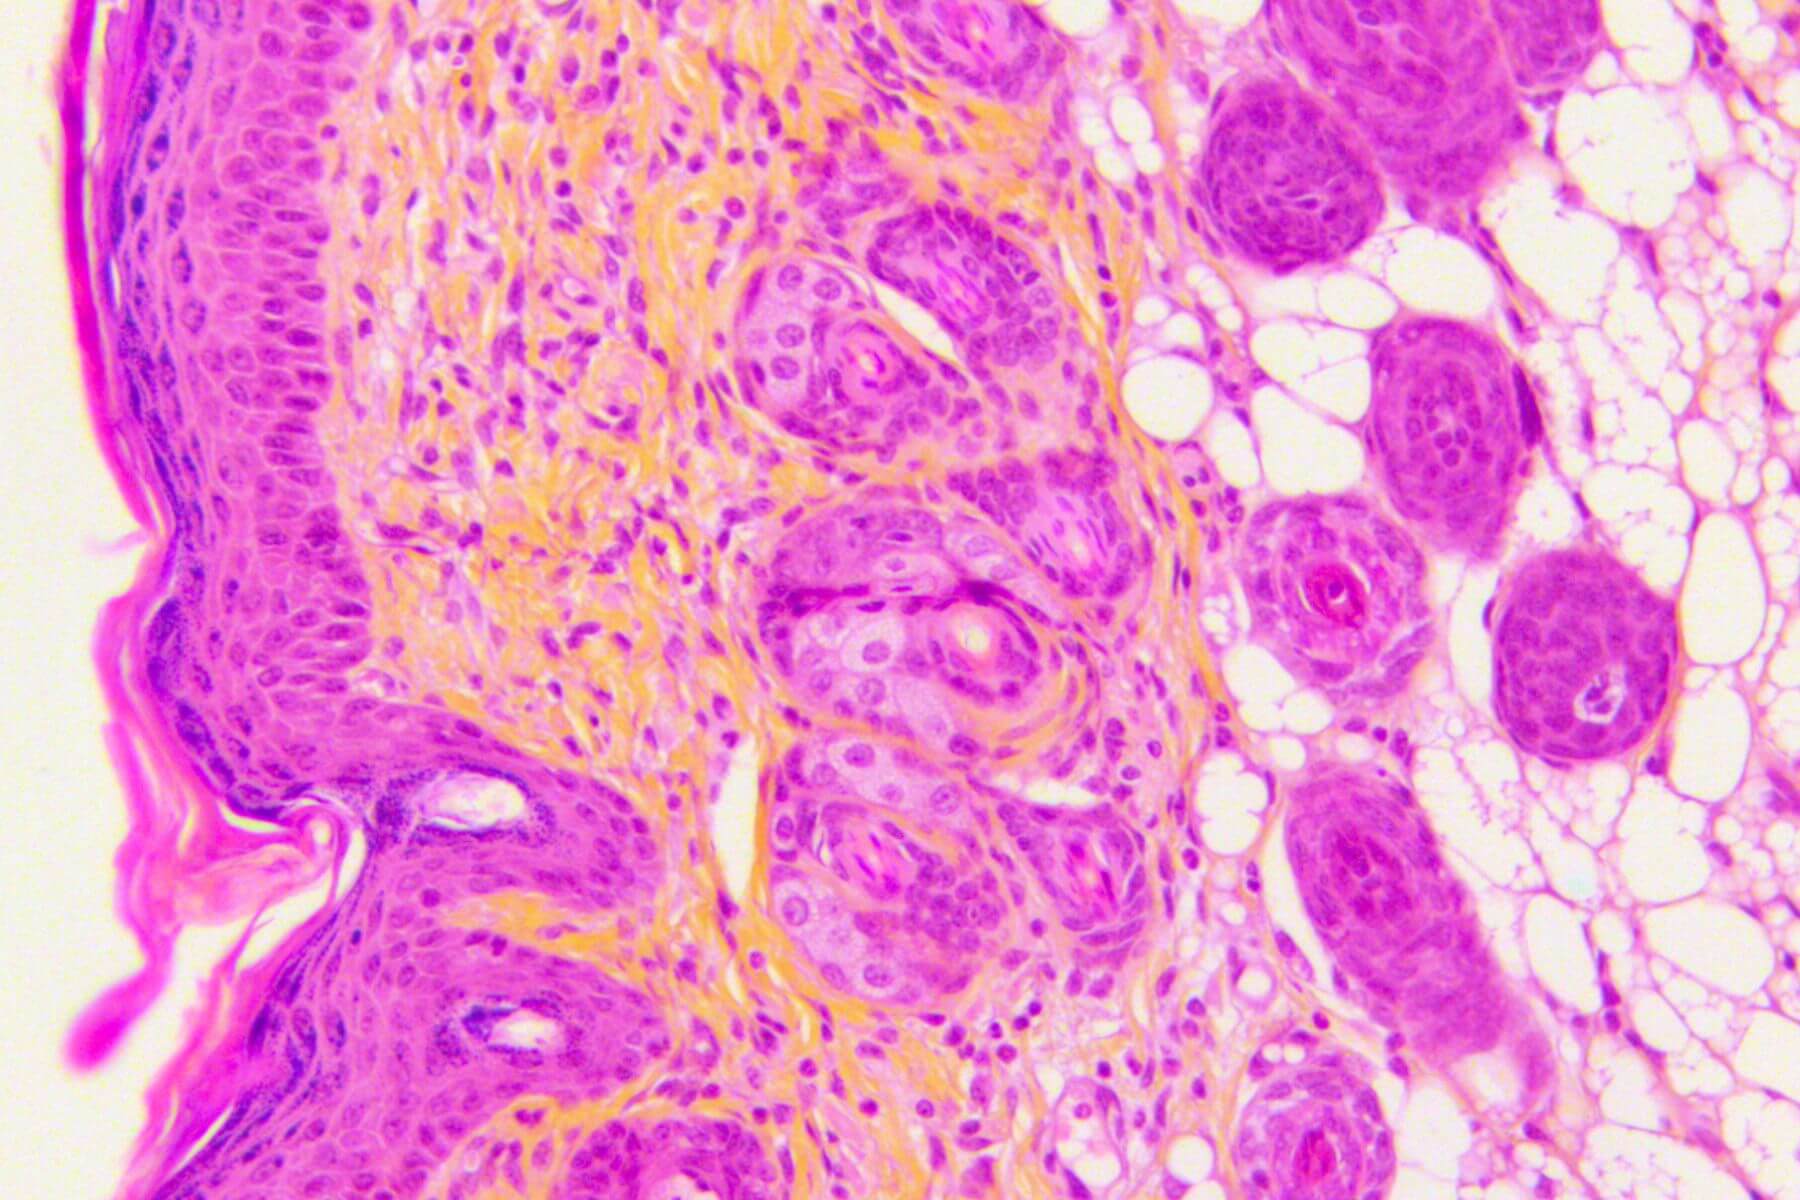

Immunohistochemistry, Immunofluorescence, and Histology

We have four areas of expertise to support the development of your drugs and medical devices: inflammatory skin diseases (Psoriasis, Atopic Dermatitis, Eczema…), wound healing (acute and chronic wounds), skin grafting (skin substitutes, organoids, biomimetic constructs…), and dermal toxicity (acute, sub‑chronic, and chronic).